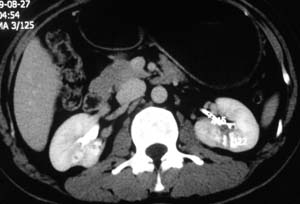

以下是引用子期在2010-3-19 20:47:00的发言:[br]血管畸形的ct增强应该有明显强化,本例并不相符合。本例双肾局部的略低密度影,累及肾盂,局部皮质明显变薄、内陷,增强扫描有轻度的强化,应考虑为炎性病变,患者为年轻男性,累及双肾的感染以结核较常见,可以没有明显的临床症状,尿中有时候也并不能查出什么;肾脓肿常有明显感染中毒症状,本例不符,另外一般的肾盂肾炎或肾小球肾炎通过小便就可确诊,其它还不能排除的是黄色肉芽肿性肾盂肾炎,然而单凭ct一般也很难鉴别。